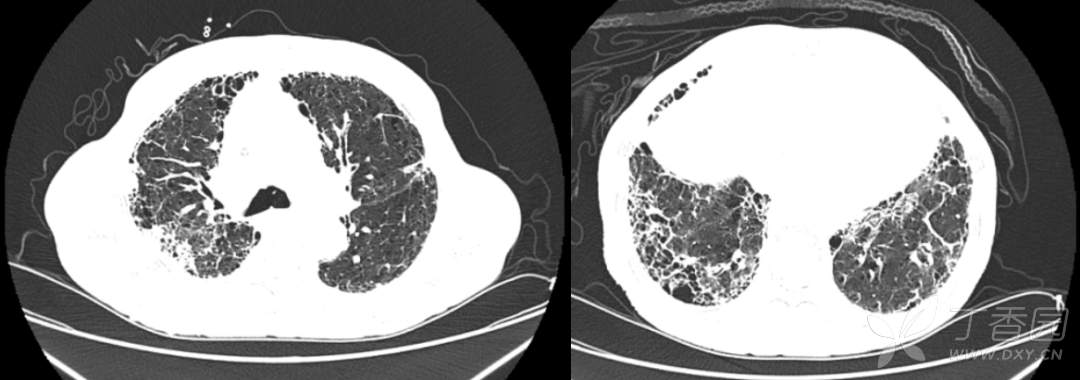

胸部 CT 提示双肺间质纤维化。

该病例其实容量管理已经到位,虽然肺部布满 B 线,但实际上是肺间质纤维化的超声表现。因为肺纤维化对胸膜的损害性更大,胸膜有明显破坏痕迹,该患者的肺部超声还可见胸膜增粗、增厚、粗糙不均匀,连续性中断,颗粒样改变或结节样改变,这是肺纤维化的超声特征。